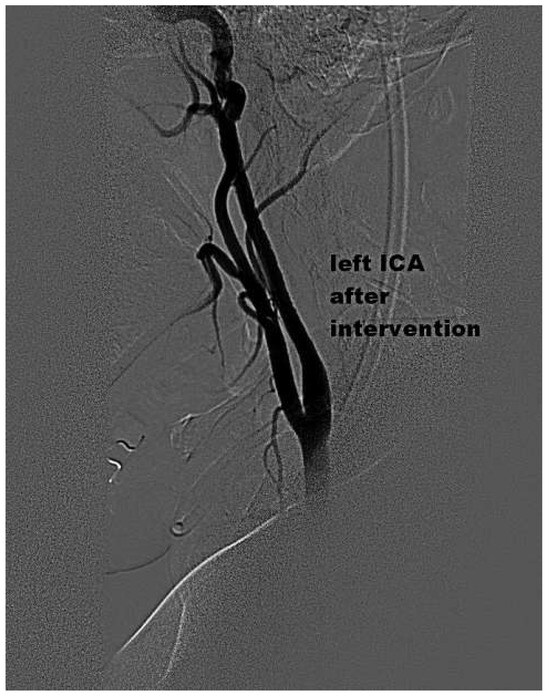

Mechanical Thrombectomy After Embolic Internal Carotid Artery Occlusion in Acute Stroke

by Christophe A. Wyss, Anahita Dastoor and Roberto Corti

Cardiovasc. Med. 2014, 17(2), 51; https://doi.org/10.4414/cvm.2014.00204 - 19 Feb 2014

A 34-year old woman presented to the emergency department with a wake-up stroke, after onset of a sensomotoric paresis of the right arm and motoric aphasia [...] Full article

Figure 1